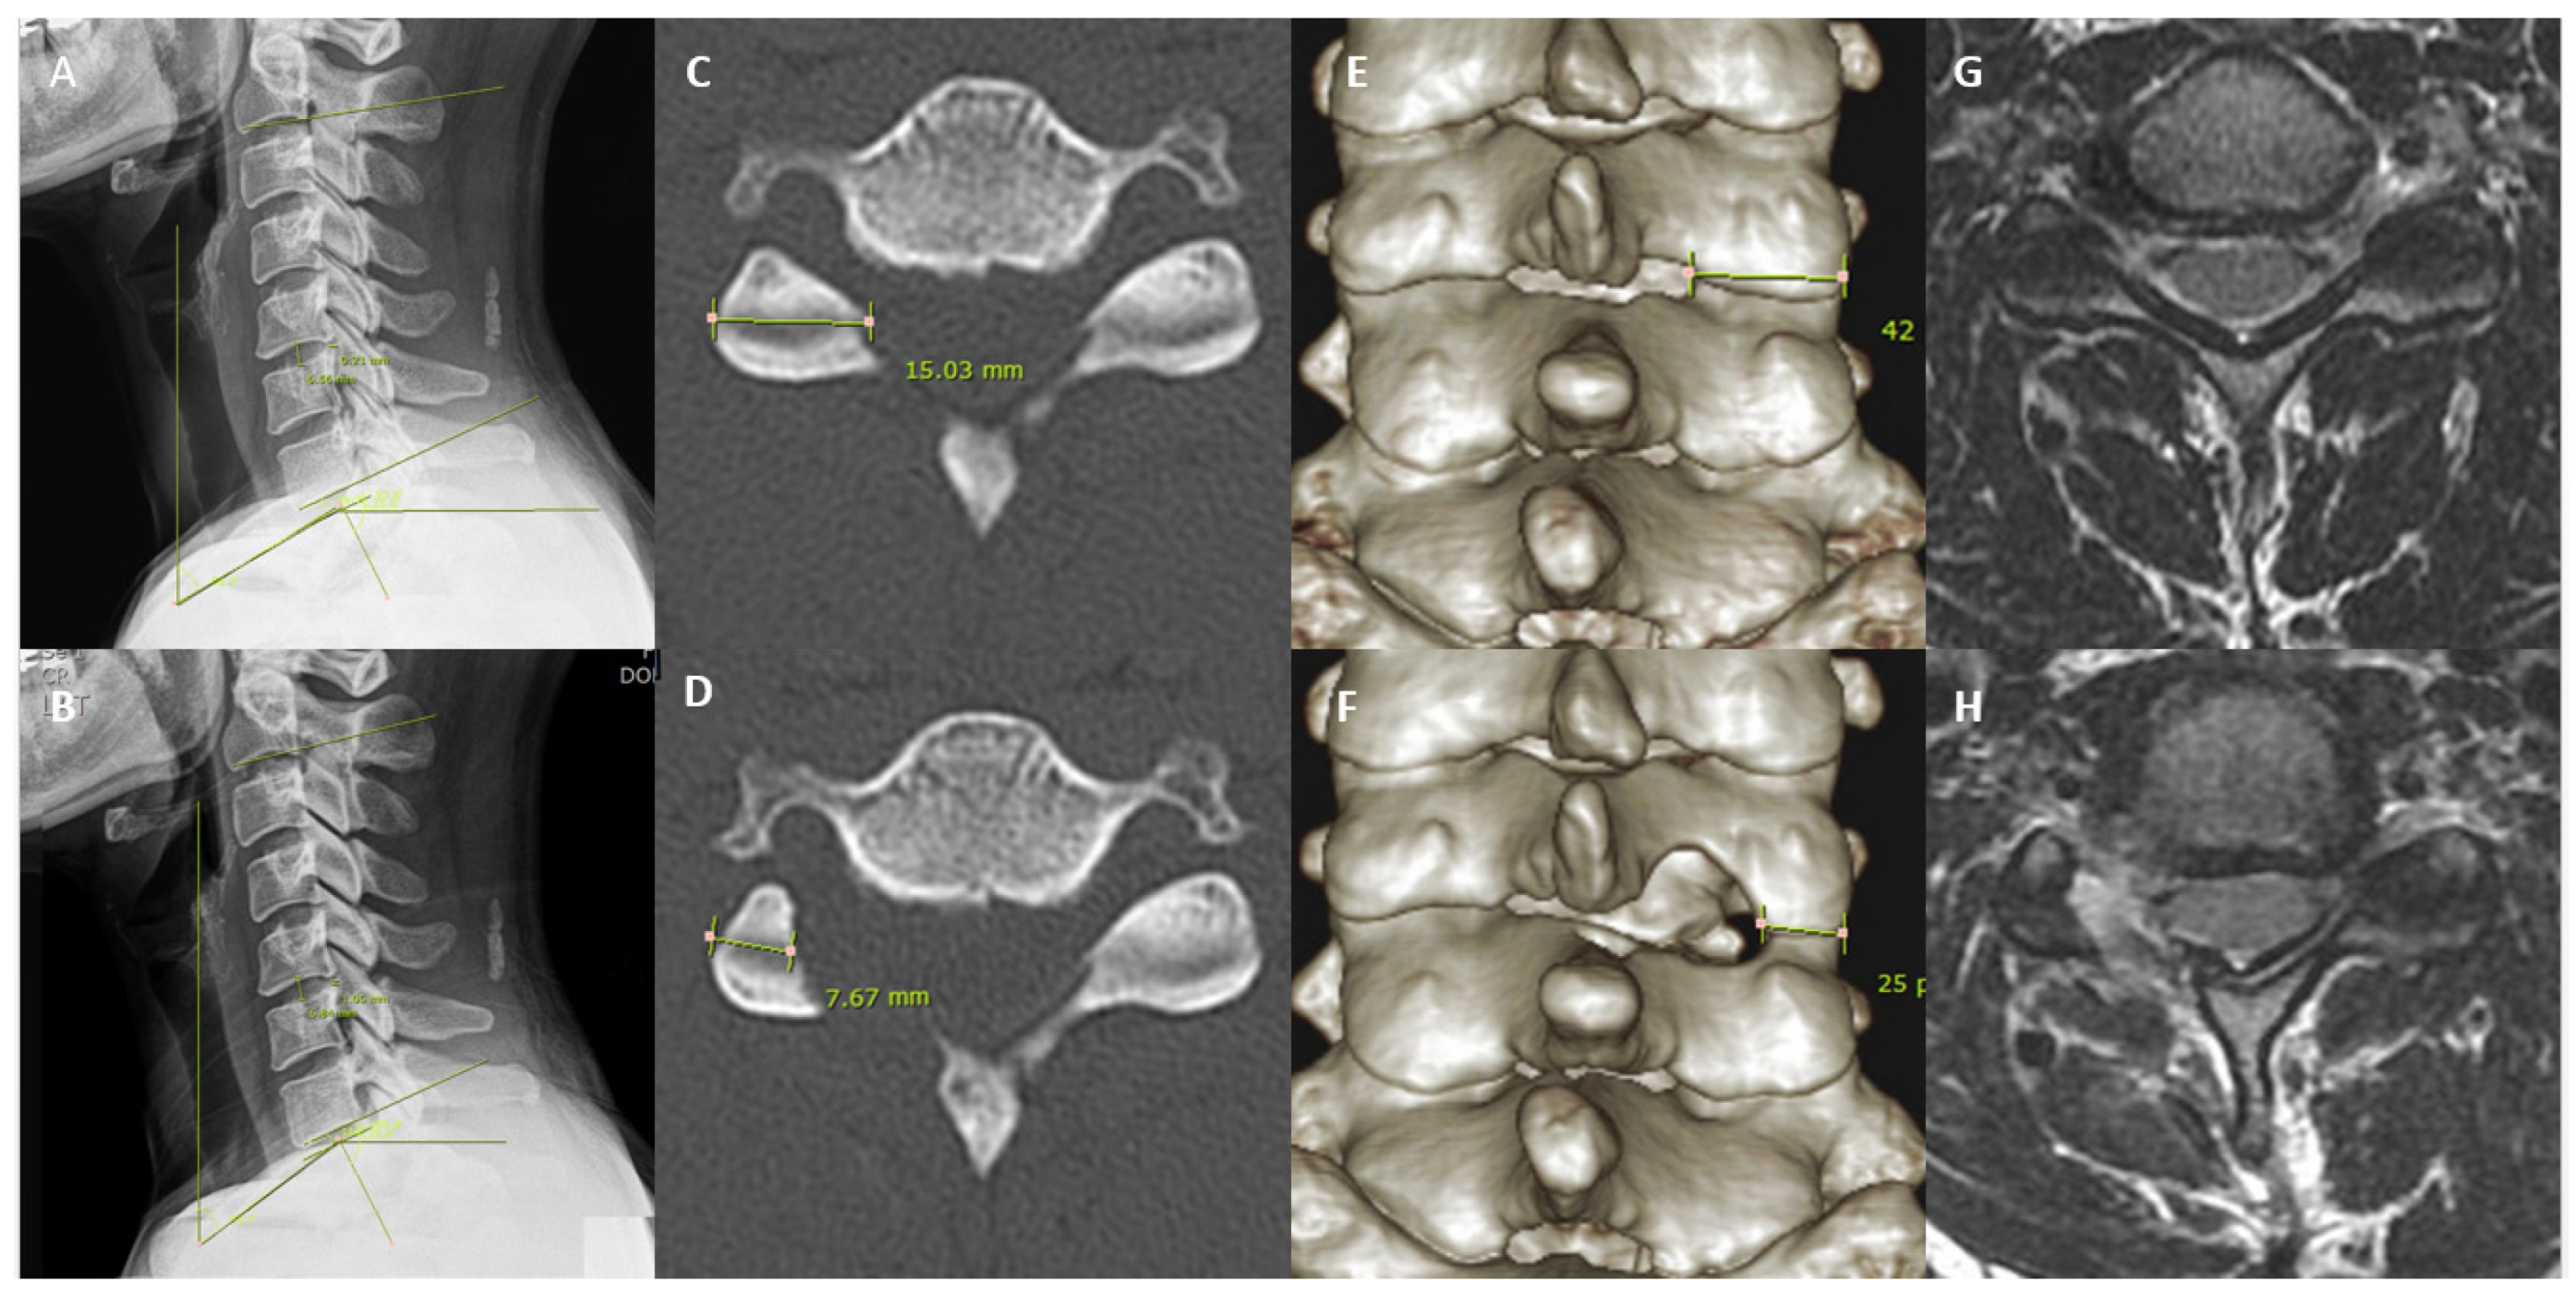

| Facet length (mm) | |||||

| Preoperative | 15 ± 1.79 | - | - | - | - |

| Postoperative | 7.89 ± 2.4 | <0.001 * | - | - | - |

| Facet area (mm3) | |||||

| Preoperative | 44.21 ± 6.78 | - | - | - | - |

| Postoperative | 21.55 ± 7.27 | <0.001 * | - | - | - |

| Disc height (mm) | |||||

| Preoperative | 6.41 ± 1.39 | - | - | - | - |

| Postoperative | 6.38 ± 1.41 | 0.354 | - | - | - |